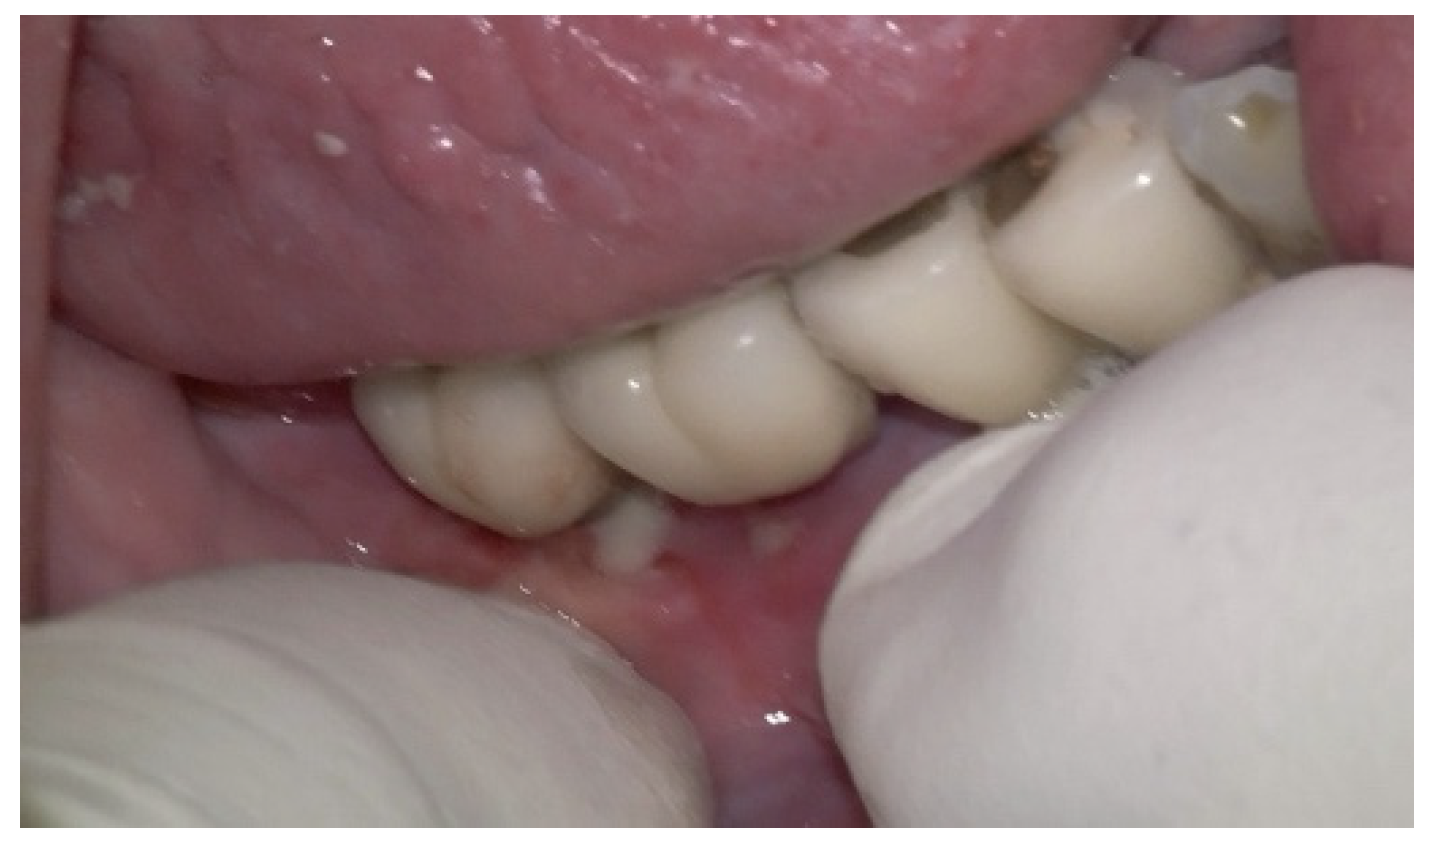

A generally healthy 63-year-old female presented to our clinic with chief complaints of foul odor and occasional pain emanating from dental implants located in the mandibular right quadrant (from implants #42 to #47). Clinical examination revealed peri-implantitis, with a high level of BoP and suppuration around the affected implants. The radiographic evaluation confirmed moderate-to-severe vertical bone loss, consistent with a diagnosis of peri-implantitis (Figure 19).

Before the surgical management following the Quadrant protocol, the fixed prosthesis was removed (Figure 20), and the region was cleaned. The surgical procedure involved a BSF, which was reflected lingually (Figure 21a,b) to facilitate access to the affected implant surfaces. With optimal access, thorough removal of granulation tissue occurred, minimizing the risk of lingual nerve damage and allowing for control of the flap.

Figure 19. (a) Initial clinical assessment; (b) Periapical X-ray presenting the measurements (red arrows) from the platform to the bone; (c) The panoramic view shows the vertical bone loss found at baseline.